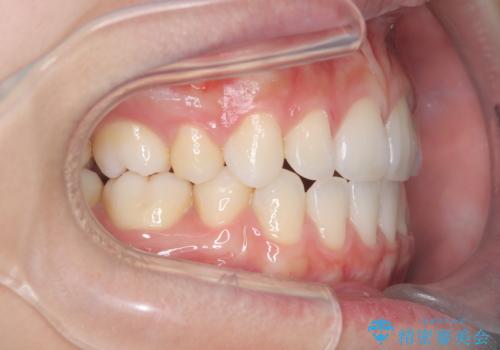

- 治療計画

上下左右の第一小臼歯を抜歯し、クリアブラケット(白い装置)とメタルワイヤーを使用して矯正を開始。初期には犬歯のアーチ内への整列を優先し、中盤からは前歯と奥歯の咬合関係の調整を進めました。審美性に優れた装置を使用したことで、治療中も目立ちにくく、見た目へのストレスが少ない点も評価されています。全体の治療は1年半で完了し、見た目・噛み合わせともに大きく改善。患者本人も「短期間でここまで変わるとは思わなかった」と満足されていました。